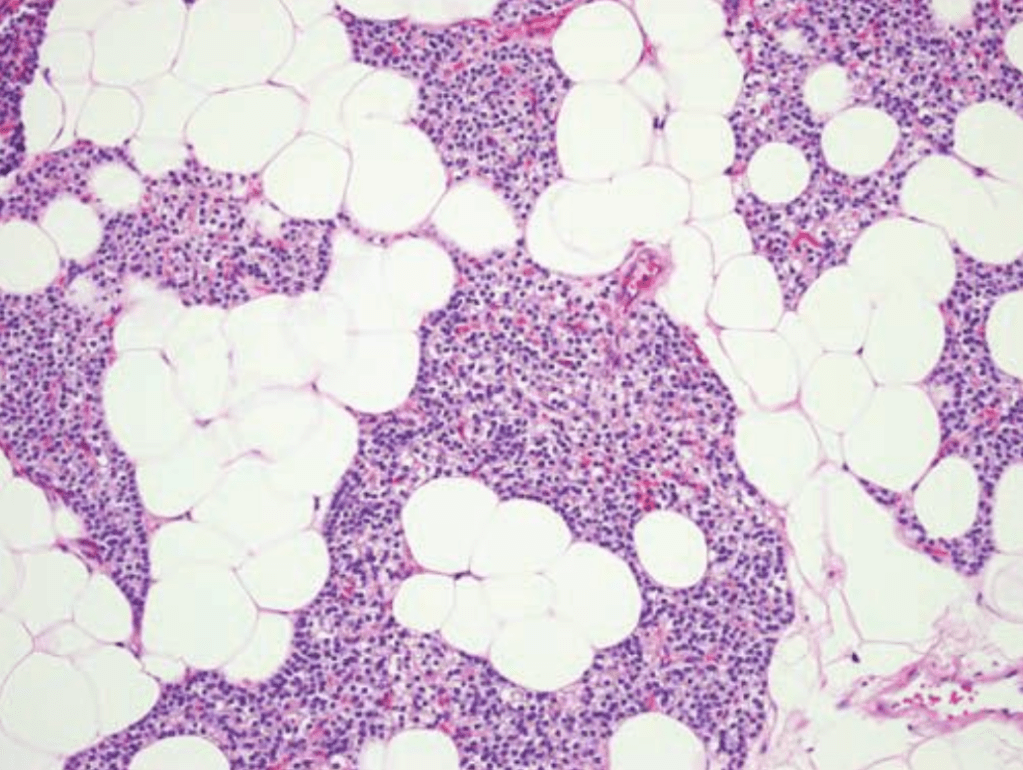

- Histologically, parathyroid glands are composed of:

- Chief cells and oxyphil cells arranged in trabeculae, within a stroma composed primarily of adipose cells (Figure)

- The parathyroid glands of infants and children:

- Are composed mainly of chief cells:

- Which produce parathyroid hormone (PTH)

- Acidophilic, mitochondria-rich oxyphil cellsL:

- Are derived from chief cells:

- Can be seen around puberty:

- They increase in numbers in adulthood

- A third group of cells, known as water-clear cells:

- Also are derived from chief cells

- Are present in small numbers, and are rich in glycogen

- Although most oxyphil and water-clear cells retain the ability to secrete PTH:

- Their functional significance is not known.